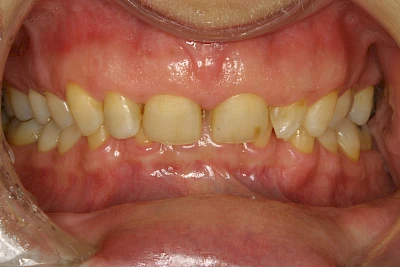

Über die Zeit können verschiedene Prozesse die Zahnhartsubstanzen aufzehren:

- Abnutzung durch Kauen (Abrasion) oder duch durch übermäßiges Knirschen bzw. Pressen (Attrition)

- Säurebedingte Auswaschung (Erosion)

- Knirschen bzw. Pressen und ungünstige Putztechnik (Druck): keilförmige Defekte

Die Zähne können dabei auf Reize (warm, kalt, süß, sauer) oder auch beim Zähneputzen empfindlich oder schmerzhaft sein. In allen diesen Fällen ist es sinnvoll, den Zahnarzt zu kontaktieren und das weitere Vorgehen abzustimmen.